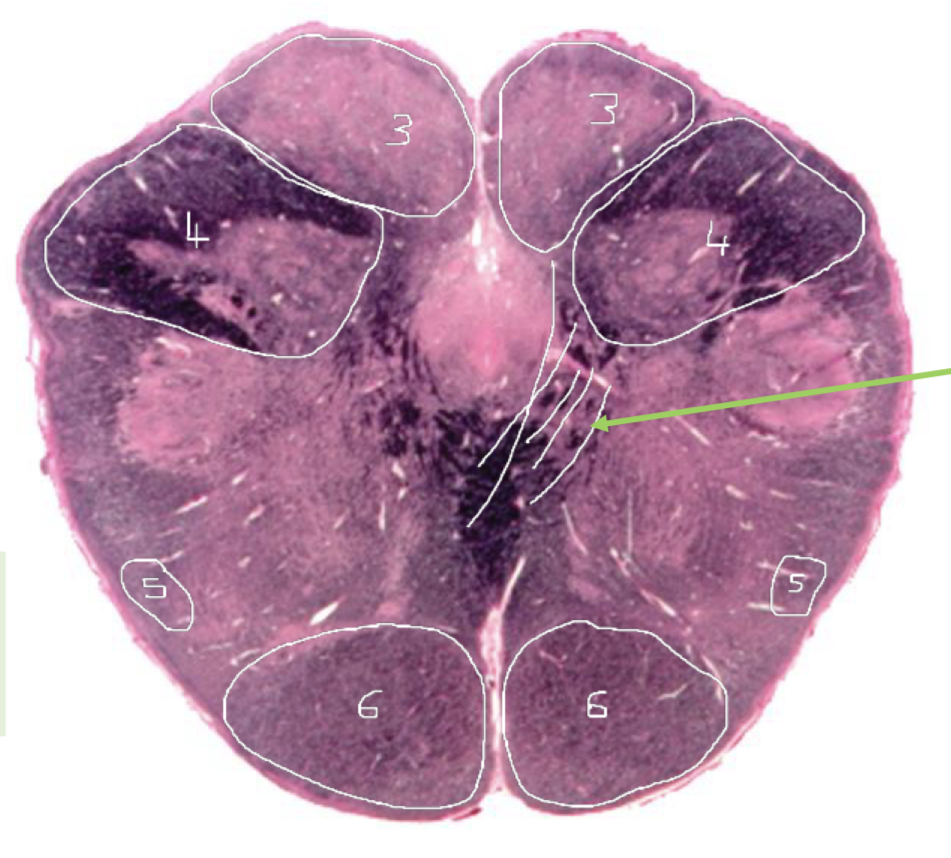

3

CST - Caudal Pons

4

4th Ventricle - Caudal Pons

5

Inferior Cerebellar Peduncle - Caudal Pons

6

Middle Cerebellar Peduncle - Caudal Pons

7

Superior Cerebellar Peduncle - Caudal Pons

8

Dentate Nuclei (Cerebellum) - Caudal Pons

9

Inferior Olivary Nucleus - Caudal Pons

10

Medial Longitudinal Fasciculus (MLF) - Caudal Pons